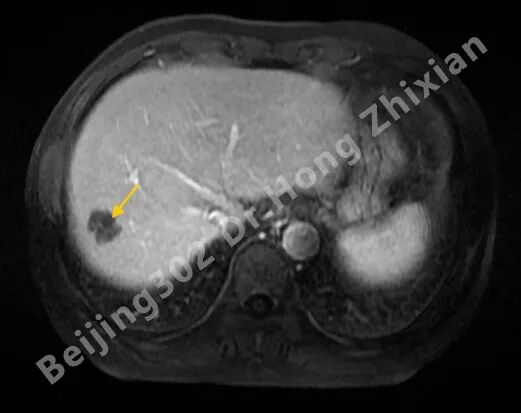

临床随笔丨肝癌术前新辅助治疗:“更优选择”还是“过度治疗”?

病例简介